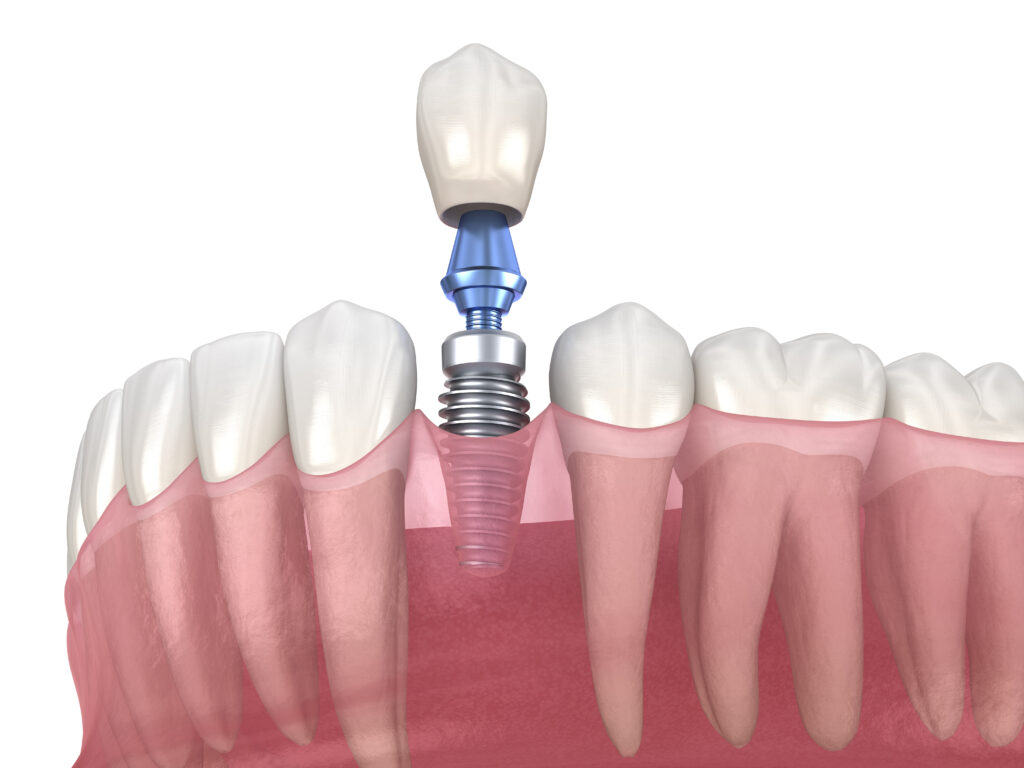

임플란트는 자연치아가 상실되었을 때

치아의 기능을 대신할 수 있는

치료방법으로 잇몸뼈에 구조물을

직접 심는 방식으로 진행됩니다.

.

임플란트의 구조는 세 가지로

나누는데 치아의 뿌리 역할을

하는 인공 뿌리(fixture),

인공 뿌리와 보철물을 연결해 주는

중간 기둥 역할의 지대주(abutment),

치아 모형의 최종 보철물(crown)로

나누어지며, 기존의 틀니나 브릿지에 비해

고난도 시술에 해당하므로

누가 식립을 하느냐에 따라

결과가 천차만별로 달라질 수 있습니다.